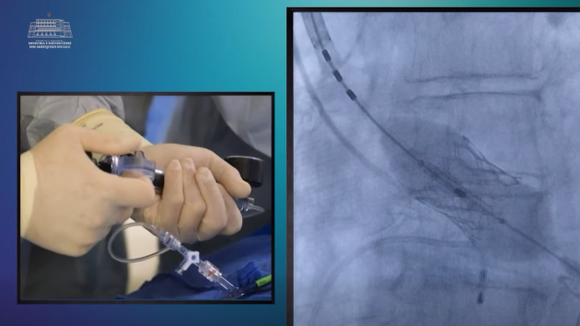

Kirurgjia koronare miniinvazive realizohet në Qendrën Spitalore Universitare “Shefqet Ndroqi”